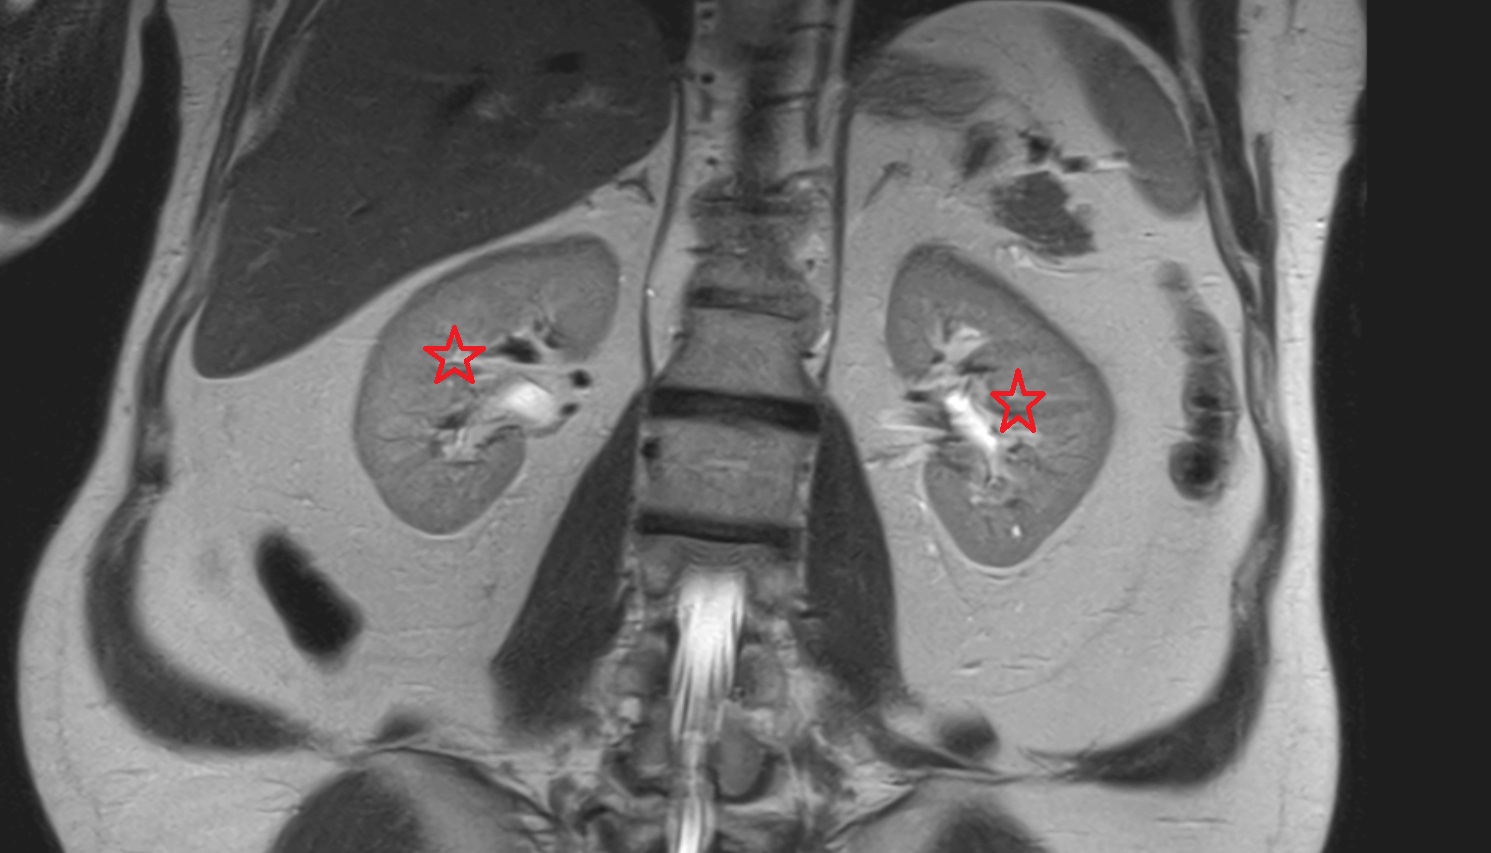

- kidneys

- Right kidney

- Left kidney

- Kidney cortex (Renal cortex)

- Renal medulla

- Renal pyramids

- Ureteropelvic junction

- Renal pelvis